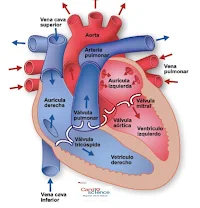

- Aurícula dereita.

- Aurícula esquerda.

- Ventrículo dereito.

- Ventrículo esquerdo.

Estas cámaras teñen válvulas que péchanse con cada latido cardíaco, isto provoca que o sangue flúa nunha soa dirección.